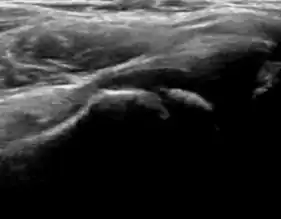

During childhood, ultrasound is a quick method to assess hip pain and quite often may be used to avoid use of irradiating techniques, such as radiography or CT. Ultrasound allows evaluation of joint effusion, synovial thickening and neovascularity, the bone/cartilage contour, and the femoral head-neck alignment. Although sonography is extremely sensitive in detecting increased synovial fluid, it is nonspecific and cannot be used with accuracy to determine the type of fluid. Transient synovitis of the hip, despite being the most frequent cause of pain in children between 3 and 10 years, remains a diagnosis of exclusion. It usually shows anechoic fluid, but echogenic fluid can also be found. The effusion is considered pathologic when it is measured at >2 mm in thickness. The differential diagnosis is wide, including osteomyelitis, septic arthritis, primary or metastatic lesions, LCPD, and SCFE. Discrimination from septic arthritis is challenging, often requiring joint aspiration. In septic arthritis, US is able to demonstrate a hip joint effusion, synovial thickening, and cartilage damage, although the appearances are nonspecific.[1]

A step between the head and the physis can be detected in children with SCFE, while abnormalities in the femoral head contour may suggest the presence of LCPD. In both cases, radiographs are mandatory to confirm diagnosis and severity (Figure 12).[1]

Figure 12: